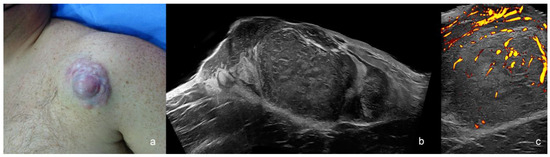

1.3.1. Basal Cell Carcinoma (BCC)

Primary BCC Tumor

| Basal Cell Carcinoma | hypoechoic, hyperechoic spots, oval, round, elongated, rosary-bead shape, variants with anechoic spaces, irregular borders | low degree |